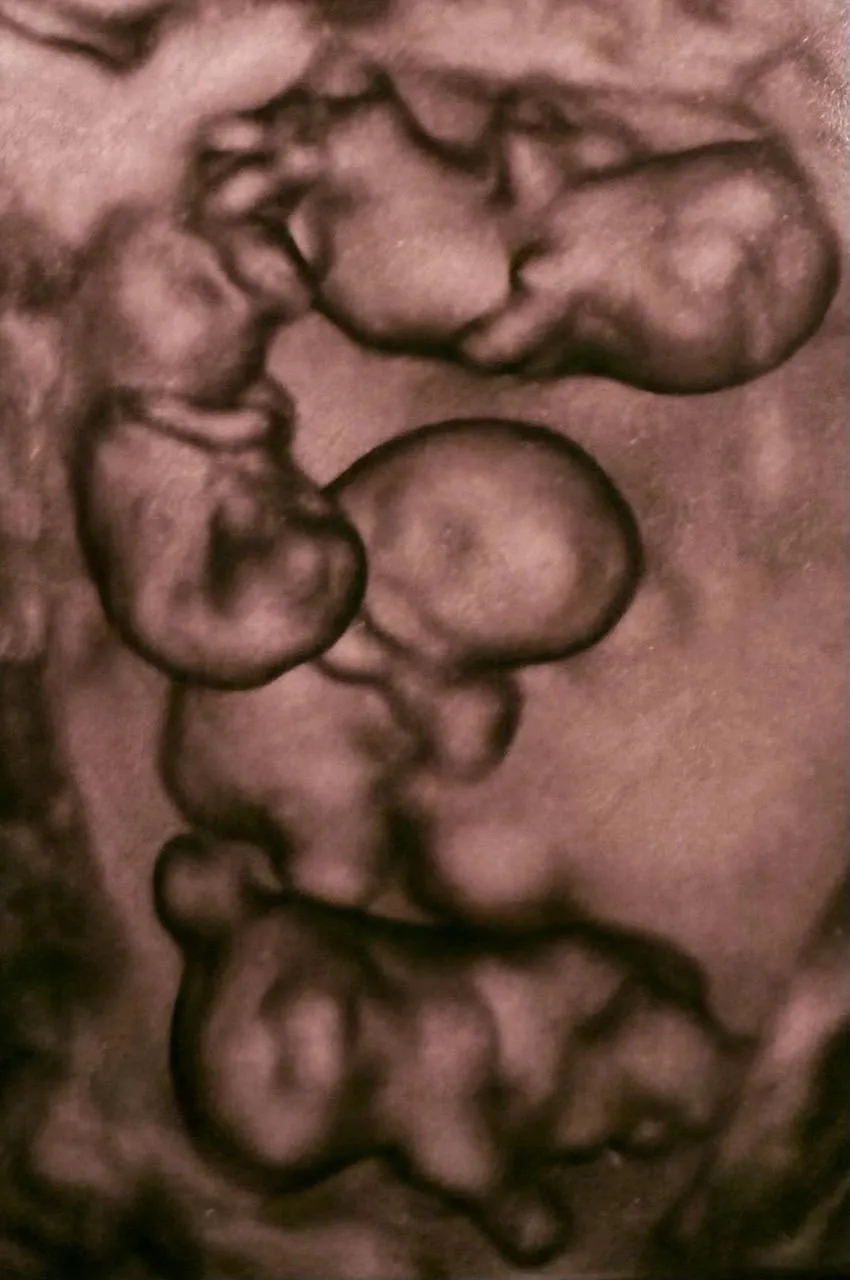

В России впервые зафиксирован случай рождения однояйцевой четверни — редкое событие, которое встречается примерно раз на 15,5 млн родов.

Все четверо новорождённых — девочки-близнецы. Они появились на свет в Санкт-Петербурге с весом от 1360 до 1640 граммов и ростом от 37 до 41 сантиметра. В мире известно около 15 таких случаев, большинство из которых также являются девочками.